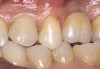

Second-stage surgery was performed after 5 months; healing abutments were placed, and the soft tissue was allowed to heal for an additional 5 weeks. Splinted porcelain-fused-to-metal (PFM) crowns supported by custom gold abutments then were delivered (Figure 5).

Figure 4 Implant positioning; the radiograph taken 4 weeks after placement confirmed good primary stability.

Figure 5 Final implant-supported PFM restorations.